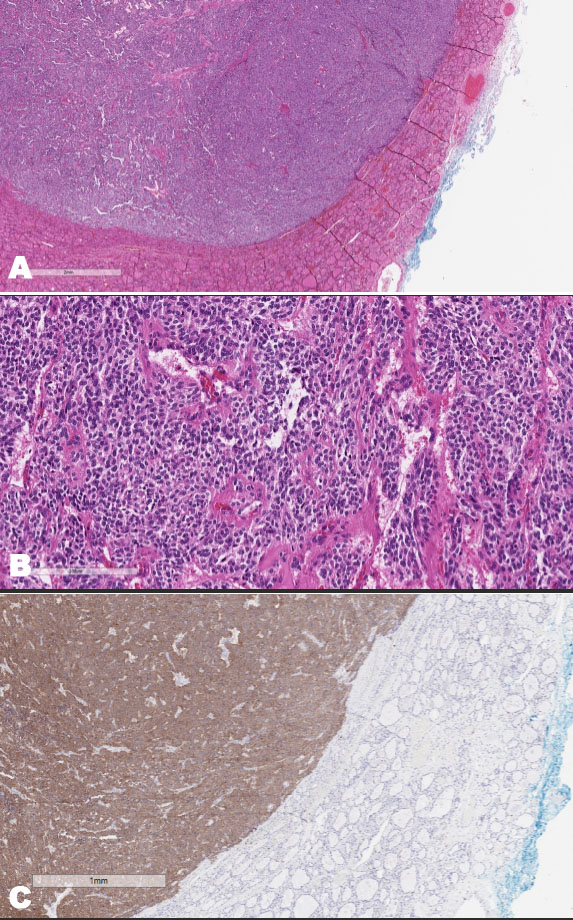

Sectioning of the right lobe of the thyroid confirmed the presence of two discrete lesions. Lesion 1 in the upper pole measured 19 × 13 11 mm and was a solid cream well-defined unencapsulated lesion. Lesion 2 occupied most of the lower mid-poles and measured 36 × 35 × 15 mm. It was an encapsulated multilobulated cream-to-hemorrhagic lesion with a focus of severe calcification in the center. Microscopic examination of the thyroid showed nodular hyperplasia of the thyroid. Parathyroid tissues were noted near the nodule. Lesion 1 was vascular, with an alveolar pattern of spindle and epithelioid cells (Figure 2).

Figure 2: (A) Thyroid paraganglioma: showing a well demarcated nodule in the thyroid (× 2). (B) Thyroid paraganglioma: showing alveolar pattern of tumor cells with granular cytoplasm with highly vascular stroma (× 20). (C) Thyroid paraganglioma: positive for synaptophysin.